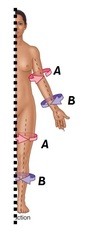

Name the types of muscle from the examples given

A - Circular

B - Pennate

C - Quadrate

D - Flat (with aponeurosis)

E - Fusiform